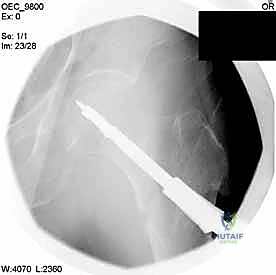

2. الرد المغلق تحت جهاز الأشعة (Closed Reduction)

قبل إجراء أي شق جراحي، يقوم الدكتور هطيف بسحب الساق وتدويرها بمهارة فائقة لإعادة العظام المكسورة إلى مكانها الطبيعي (المحاذاة التشريحية). يتم التأكد من ذلك باستخدام جهاز الأشعة السينية المتحرك داخل غرفة العمليات (C-Arm Fluoroscopy). هذه الخطوة حاسمة، فالرد الجيد يعني التئاماً ممتازاً.

4. إدخال السلك الدليلي (Guide Wire)

يتم إدخال سلك معدني رفيع جداً عبر العظم باتجاه رأس الفخذ تحت توجيه الأشعة المستمر. هذا السلك يعمل كمسار دقيق سيتبعه المسمار النهائي. يجب أن يكون السلك في الموضع الهندسي المثالي لتجنب اختراق مفصل الورك.

مجموعة من الصور الإضافية التي توضح مراحل دقيقة من العمل الجراحي المعقد الذي يجريه الأستاذ الدكتور محمد هطيف لضمان أعلى درجات الدقة الميكانيكية الحيوية: